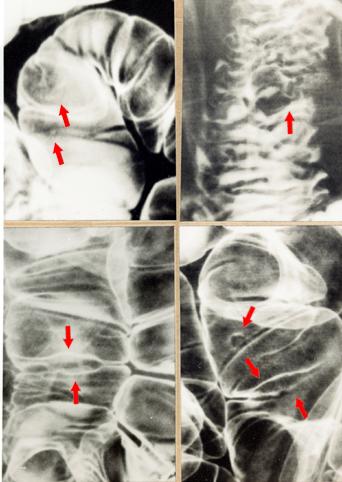

Multiple malignant lymphoma with a swelling of the ileo-cecal portion.

Tokyo Pref., Cooperative study between National Cancer Center and Kyushu Cancer Center

Malignant Lymphoma/Malignant lymphoma

Small intestine/Ileum

X-ray

15 - 19